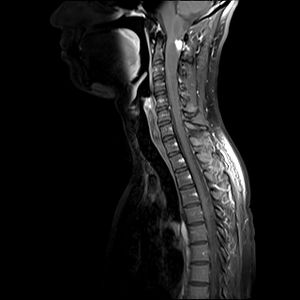

34-year-old male presented with worsening numbness and increasing weakness in right hand, progressing to proximal right upper extremity.